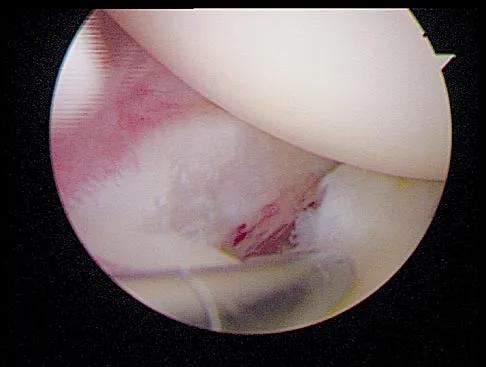

A 19-year-old soccer player feels a pop in his knee while making a cut and notes the development of an effusion over several hours. Examination reveals medial joint line tenderness, but the knee is stable to manual stress testing of all ligaments. Examination under anesthesia confirms a stable knee. What is the most critical factor in determining healing after repair of the lesion shown in Figure 14?

Explanation